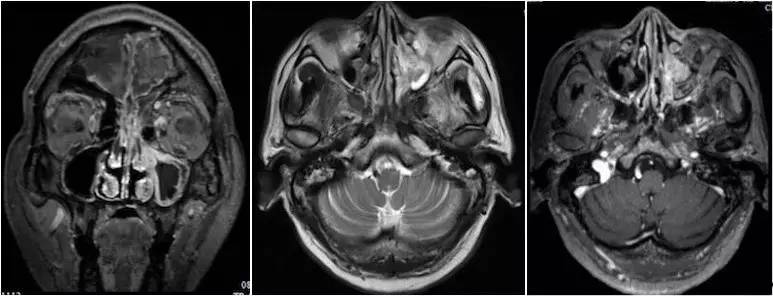

▼患者影像资料(2016-3-4)

复习病史,患者2013-7鼻内镜鼻腔肿物切除术,病理高分化腺癌,术后行同期放化疗,鼻腔局部照射65.72Gy/31f;2015-7出现前组脑神经损害症状体征,影像检查提示鼻腔及筛窦、额窦肿物,伴前颅底额叶异常强化及周围水肿,局部脑膜增厚、强化,颅底骨质不连续,考虑复发伴放射性改变;经鼻腔再次活检证实为复发;给予对症治疗症状加重,遂行PET/CT提示筛窦、双侧额叶、大脑镰、左侧眶周、海绵窦代谢增高;局部行射波刀治疗35Gy/6f,具体不详;疗后症状无明显缓解。首先双侧额叶改变MRI不能区别放射性脑坏死和肿瘤复发,可考虑进一步MRS、PWI、DWI成像提供更多的信息鉴别两者;倾向于肿瘤复发可能性大,原因如下:病变范围可能远远超出照射野;距放疗时间较短,文献报道一般放射性脑坏死中位发生时间约6年;颅底骨质破坏伴代谢增高,且与鼻腔、筛窦、左眶、海绵窦代谢一致。当然也不排除同时合并放射性损害,毕竟同时行化疗,可能较单纯放疗反应重。关于是否再行放疗改善症状,取决于前2次放疗的评价,看危及器官尤其是脑干、健侧视神经是否还能耐受;可使用卡马西平0.1、Tid,可能减轻神经痛症状;对症支持治疗方面适当应用激素、甘露醇等减轻脑水肿;也可考虑联合贝伐单抗;后续肿瘤治疗以化疗为主,请Z主任斟酌方案。